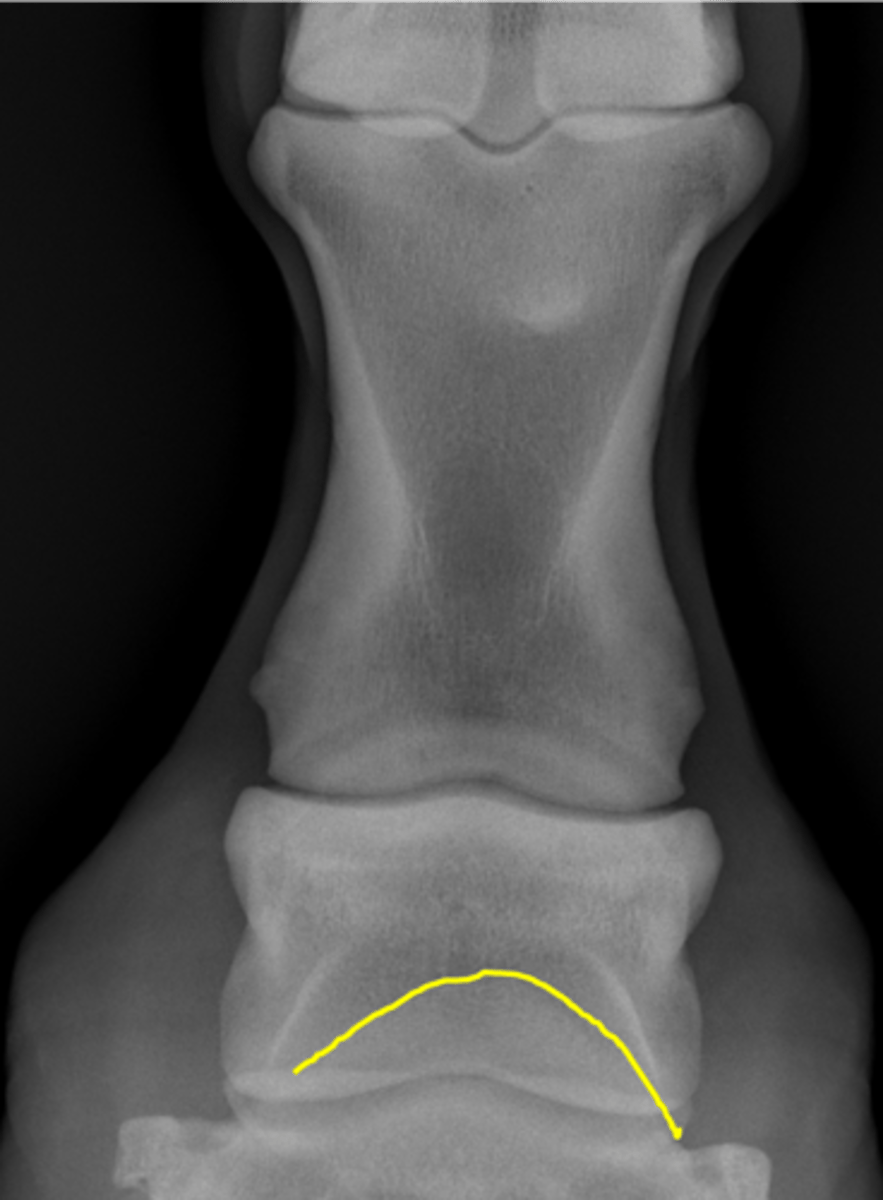

Fetlock joint, DP

ID joint and view

Proximal sesamoid bone

Sagittal ridge

Condyles of third metacarpal bone

Palmar process of P2

Proximal sesamoid bones

Sagittal ridge

Attachment of collateral ligaments

Proximal sesamoid bones

Palmar process of P1

Condyles of the third metacarpal bone